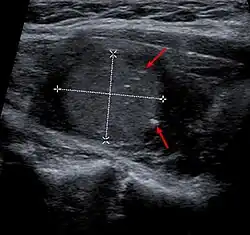

- Im Ultraschall erscheinen Schilddrüsenkarzinome meist echoarm, selten echoreich. Auch Entzündungen oder Verkalkungen können echoarm sein, Zysten sind in der Regel echofrei. Das medulläre Schilddrüsenkarzinom zeigt in der Sonographie häufig kleine Verkalkungen.